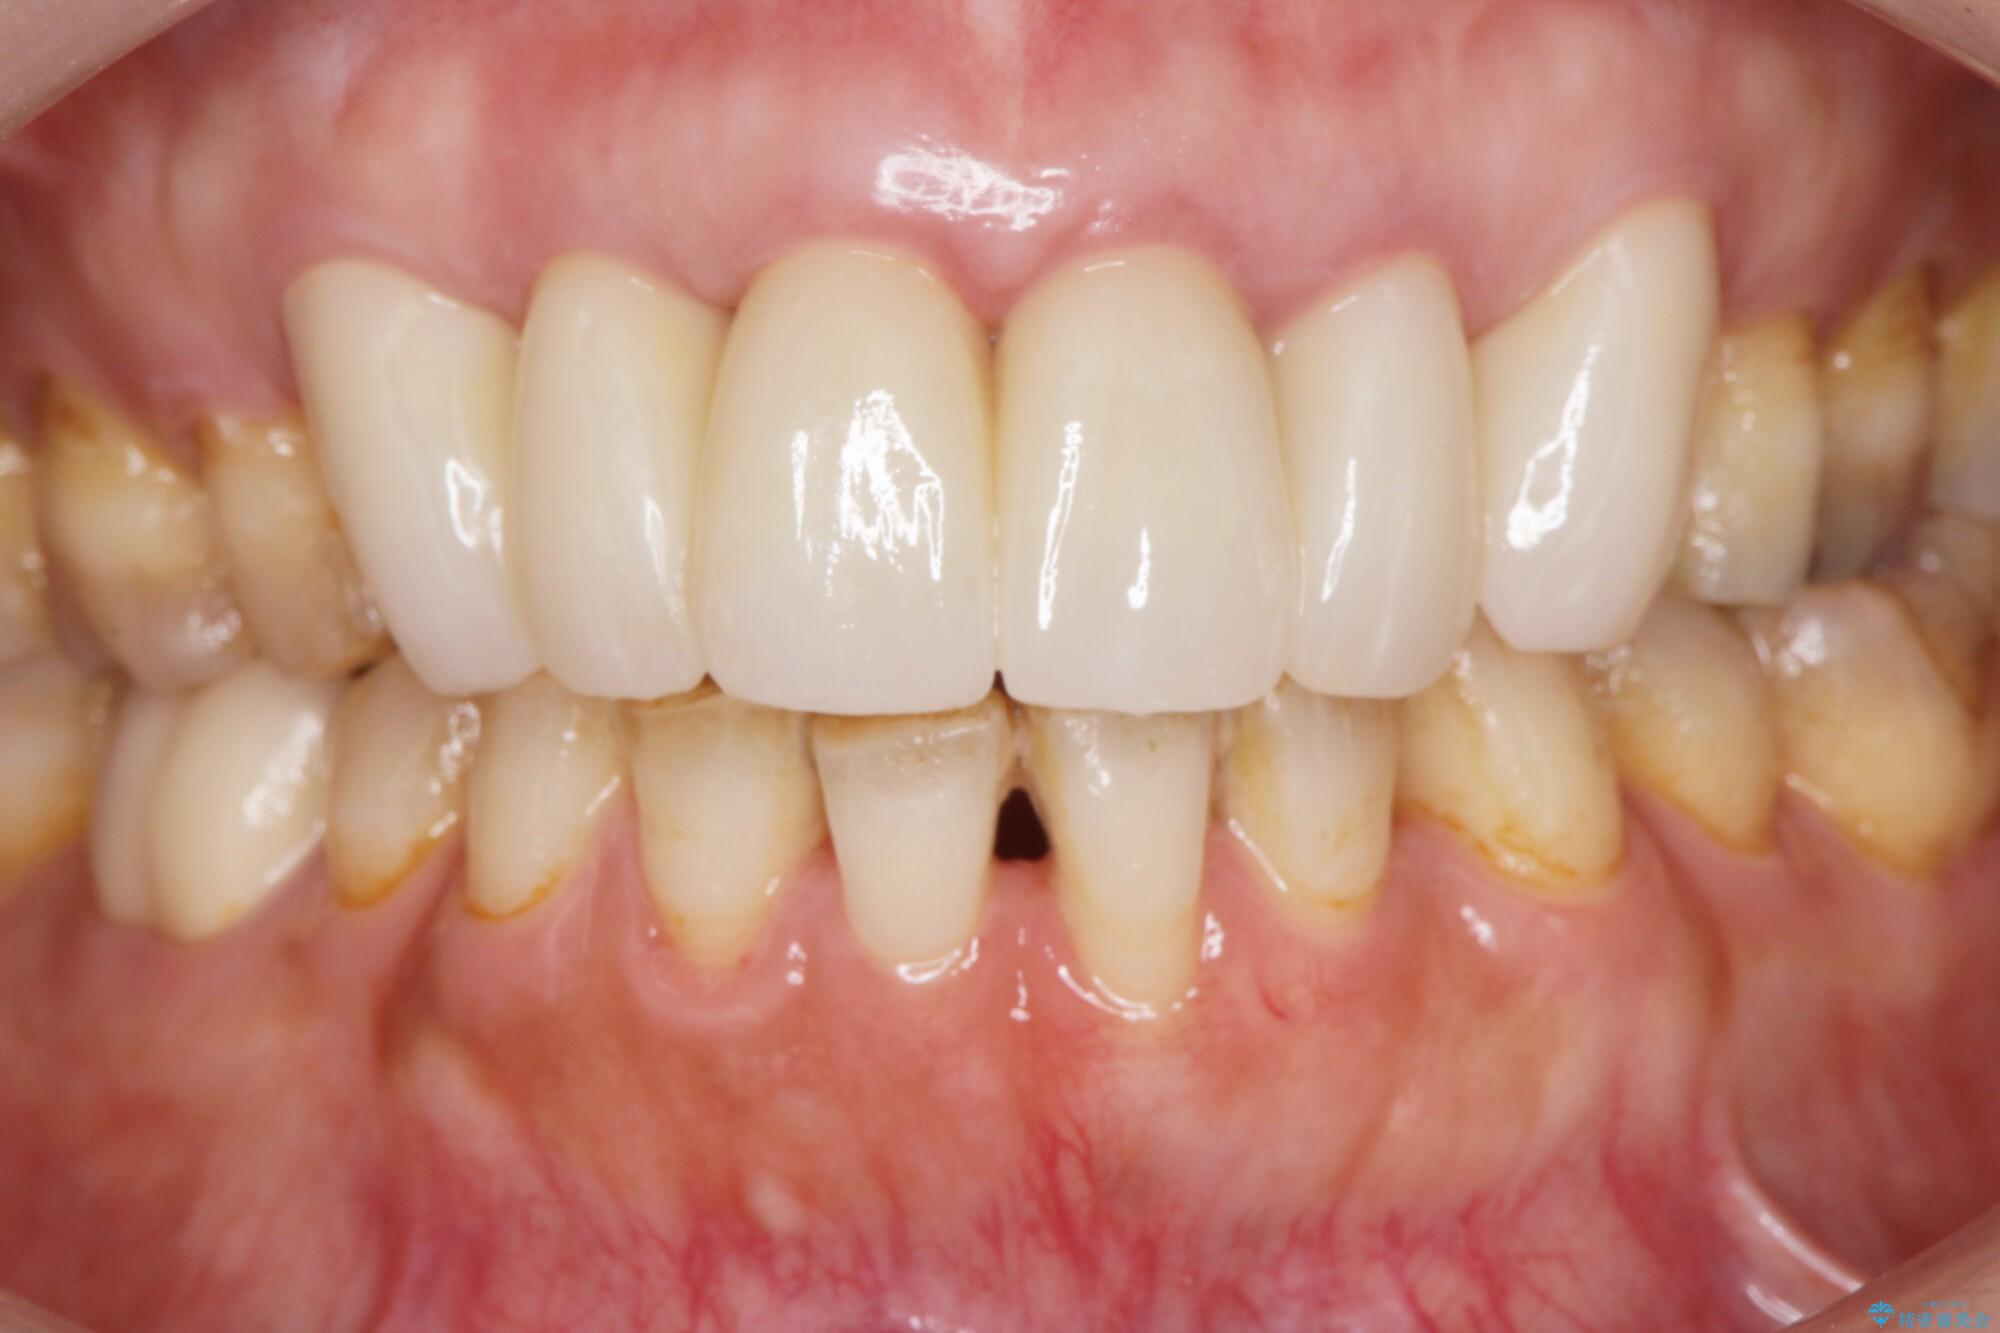

治療後について

治療には歯肉を成熟させる期間を含めて約8ヶ月間要しましたが、出血や違和感のない歯ぐきとなり大変ご満足いただけました。